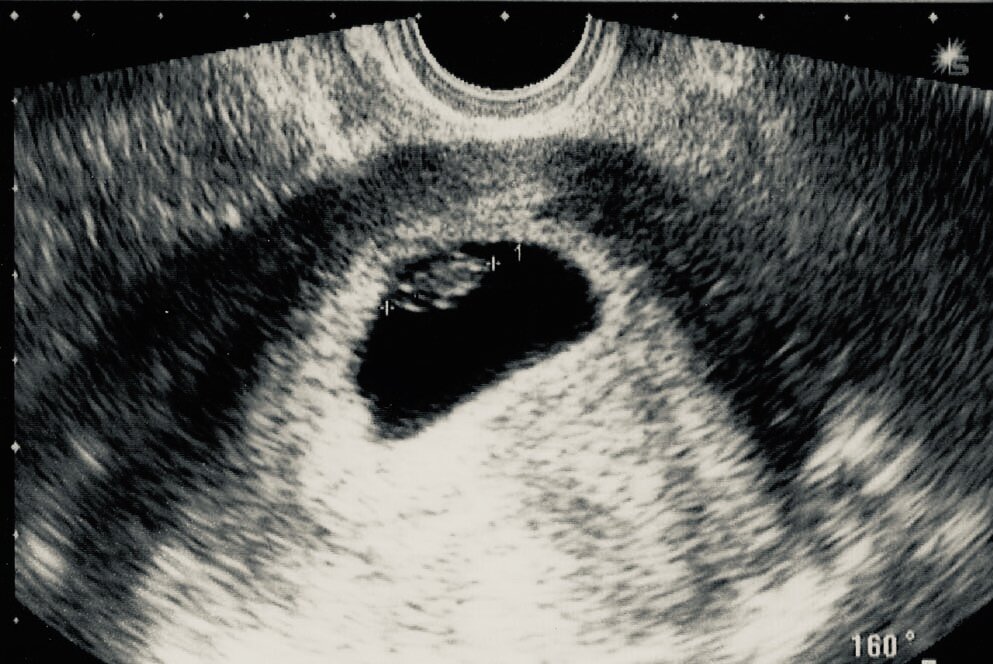

Могу вам сказать на своём опыте лучше идти в 7-8 недель , чтобы услышать сердцебиение ребёночка . Если пойти раньше , то эмбрион ещё будет очень маленьким и сердечко пока не будет слышно. Если есть опасения внематочной беременности то можно сходить в 5-6недель , чтоб увидеть плодное яйцо в матке . Раньше 6 недель его могут и не увидеть . После хождения первого узи , девушки часто задаются вопросом , когда же идти становится на учёт ? Могу сказать на своём опыте что , если ничего не беспокоит и нет каких выделений и тянущих болей . То можно спокойно ждать до 9-11 недель . А если все таки присутствуют жалобы , то срочно нужно обратиться за помощью к врачу . Например : сильные боли , которые напоминают боль при месячных , кровянистые выделения и не дай бог алая кровь . До похода к врачу можно принимать фолиевую кислоту 1 мг в сутки , как написано в инструкции по применению . А уже потом врач будет корректировать дозировку при необходимости . Фолиевая кислота необходима для форми